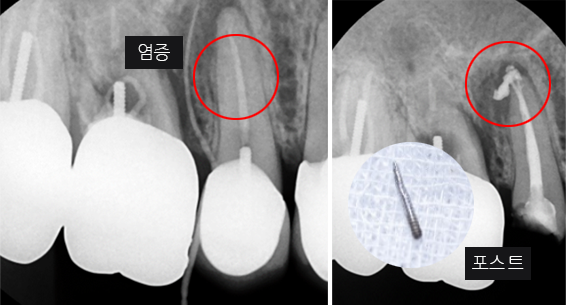

신경관이 막혀 있는 경우 재 신경치료로 낫지 않는 경우, 포스트가 있어 재 신경 치료를 할 수 없는 경우, 치아 뿌리까지 염증이 심하지만 이러한 염증을 제거 할 수 없는 경우, 고운미소 치과에서는 치조골 주위 염증조직을 제거하는 치근단절제술을 시행합니다.

기존 신경치료는 양호한 상태이나 치근부위에

염증과 치조골 소실이 진행 중

치아 뿌리 쪽 잇몸을 절개하고 치조골 부위의

염증조직을 제거. (난이도 중)

충치가 심해져 세균이 이 신경관까지 침투하면 심한 통증과 함께 염증이 생기고 치아뿌리까지 염증이 내려와 치아가 흔들리고 최후에는 치아를 잃게 됩니다. 그렇게 되기 전에 오염된 신경관을 치료하고 생체친화적 치과재료로 신경관을 채워주는 근관치료(신경치료)를 시행합니다.

지속적인 통증과 잇몸염증

기존 포스트 제거

근관내 약재 삽입

재 신경치료(난이도 상)